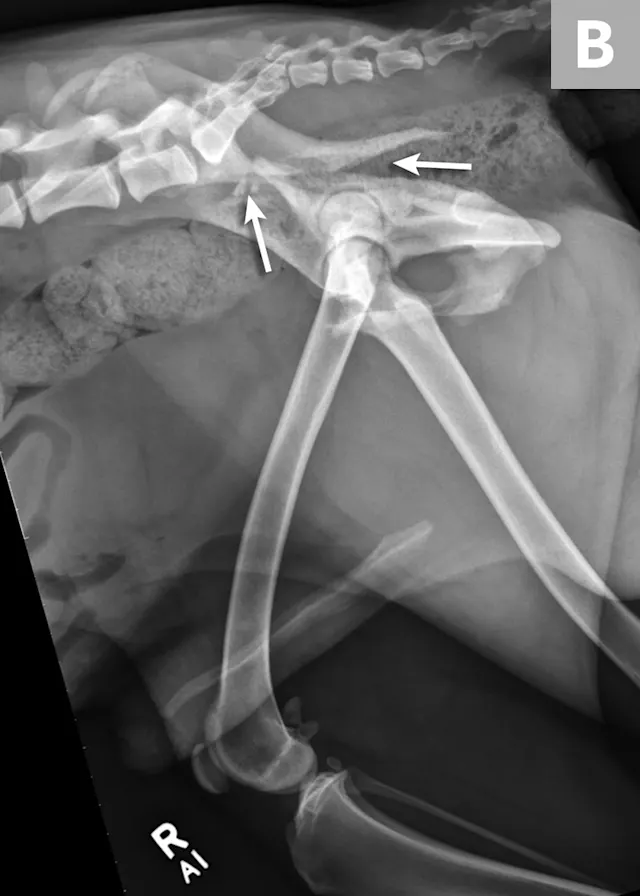

FIGURE 4A

Postoperative ventrodorsal (A) and lateral (B) projection images of the same dog in Figure 2. Fracture reduction was achieved with cross pins and a figure-eight hemicerclage wire (black arrows). Reduction was protected via application of a locking string-of-pearls neutralization plate (solid white arrows). To gain access to the full extent of the fracture, a greater trochanteric osteotomy was performed and stabilized with a positional screw and pin (dashed arrows). The ventrodorsal postoperative radiograph revealed a sacral fracture not previously appreciated (arrowhead). The fracture was successfully treated with conservative management.